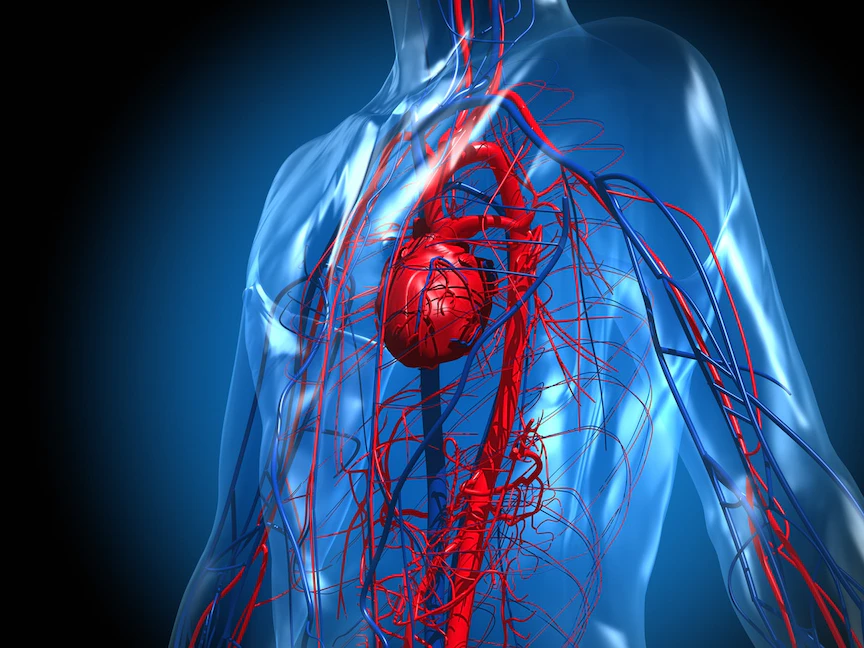

الرفرفة الأذينية، هي أحد أنواع اضطرابات نُظم القلب، وتنجم عن مشكلة في النظام الكهربائي بالقلب، حيث تنبض الحجرتان العلويتان (الأذينان) بسرعة كبيرة.

وتجعل هذه المشكلة القلب ينبض بنظم سريع، ولكنه منتظم عادةً، وبالرغم من أنه قد لا تظهر أي أعراض على الأشخاص المصابين بالرفرفة الأذينية، إلا أن هذا الاضطراب يُزيد من خطر الإصابة بالسكتة الدماغية، وفشل القلب، ومضاعفات أخرى.

وتشبه الرفرفة الأذينية الرجفان الأذيني، وهو أحد الاضطرابات الشائعة التي تتسبب في نبض القلب بشكل غير طبيعي. ومع ذلك، يكون نظم القلب في الأذينين أكثر انتظاماً وأقل اضطراباً في الرفرفة الأذينية مقارنة بإصابات الرجفان الأذيني.

وفي بعض الأحيان، قد تتعرض إلى نوبات من الرفرفة الأذينية والرجفان الأذيني معاً.

وتوجد علاجات فعَّالة للرفرفة الأذينية، تشمل الأدوية أو الإجراءات التي تهدف إلى إحداث تندب في مناطق صغيرة من أنسجة القلب (الاستئصال).